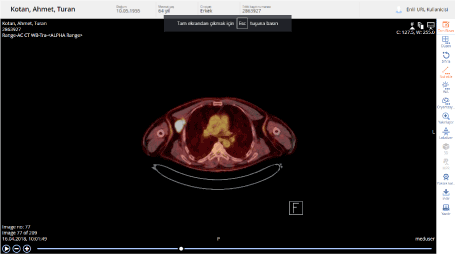

The patient's Positron emission tomography (PET/CT) showed multiple lymphadenopathies with a diameter of 3.6 cm with pathological glucose metabolism increases in the right axillary region Standardized Uptake Value (SUVmax: 42.6). Pathologic glucose metabolism increases were observed in 2 adjacent lymph nodes (SUVmax: 31.9) in the right infraclavicular region (Figures 1 and 2).

Figure 1. Image of first relapse after curative treatment

Figure 2. Image of first relapse after curative treatment